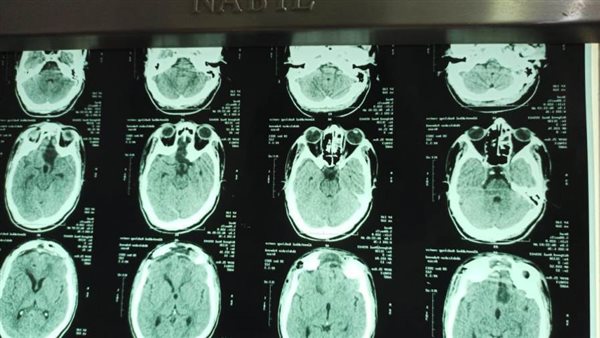

نجح فريق طبي بقسم جراحة المخ والأعصاب، بالتعاون مع قسم التخدير بمستشفي سوهاج الجامعي في استئصال اكبر الأورام من حيث الحجم بقاع الجمجمة، يبلغ ١٣٢ سنتمتر مربع، لشاب يبلغ من العمر ٢٢ سنة وإنقاذه من فقد كلي للبصر، صرح بذلك الدكتور حسان النعماني رئيس الجامعة.

وأوضح الدكتور مؤمن المأمون رئيس قسم جراحة المخ والأعصاب أن الورم الذي كان يعاني منه المريض يعد من أكبر الأورام حجماً في قاع الجمجمة، واستغرقت الجراحة اكثر من ٨ ساعات، تمت خلالها استئصال كلى للورم، وتتم المتابعة الدورية له بالعيادة الخارجية بقسم جراحة المخ والاعصاب.